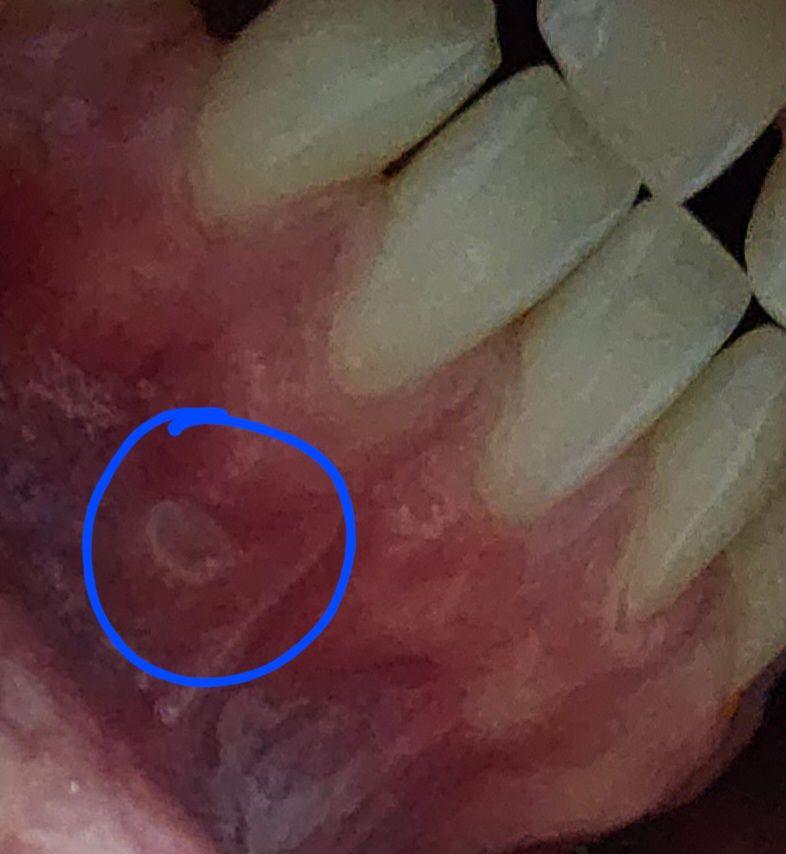

잇몸에 하얀색 염증 같은게 생겼는데 뭔지 잘 모르겠어요

제목 그대로 잇몸에 하얀색 염증 같은게 생겼습니다. 염증난 곳을 움직이면 통증이 느껴지긴하나 엄청 큰 통증은 아닙니다

구내염이라고 생각했는데 잇몸에 구내염 나본 적은 없어서 조금 의문이더라구요 잇몸에 난 거 뭘까요

사진이 좀 어두워서 그렇지 엄청 하얀색이고 가운데가 좀 파여있어요

• 사진으로 봐서는 구내염이 맞는 것 같습니다.

해당 부위는 잇몸하방의 구강전정부위입니다. 이는 볼 부위에서 연결되는 것으로 볼에 생기는 구내염과 마찬가지입니다.

사진이 어둡지만 단순 구내염으로 보입니다. 스테로이드 연고를 바르면 금방 나을 것 입니다.

사진으로 보아서는 구내염일 가능성이 큽니다. 구내염은 구강 내 다양한 부위에 나타날 수 있는 구강 내 연조직 질환 중 하나입니다. 일반적인 경우에는 자극을 주지 않고 충분한 휴식 등을 하면 2주 이내에 회복되나 시간이 지나도 회복되지 않는다면 치과 방문 후 감별 진단을 받아보셔야 합니다.